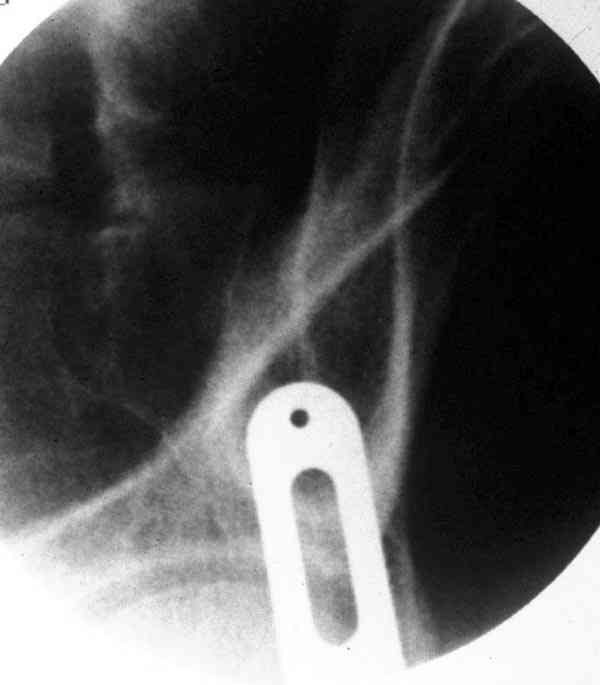

При свежем случае показана фиксация передней колонны к задней (снимки), компрессирующим винтом минимальным перкутанным методом по супраацетабулярной линии и в зависимости от состояния КПС.

iliac view

obturator tear drop view

obturator view